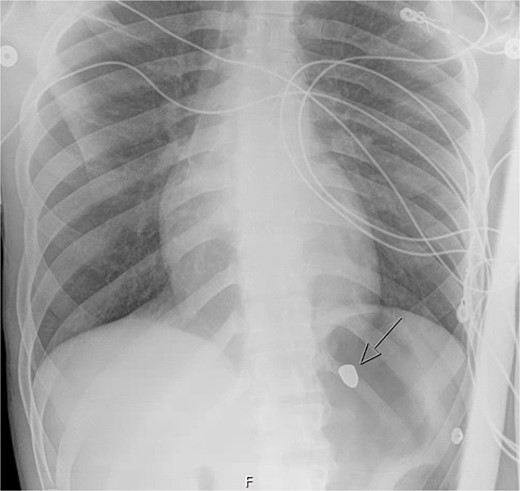

On hospital day (HD) 1, he developed ARDS and required intubation. He became hypotensive, raising concern for mediastinitis, but repeat imaging showed no new findings except that the bullet had migrated below the diaphragm (Fig. 3). Despite his septic appearance, his condition didn’t improve. He was diagnosed with severe AIDS (CD-4 count <100 cells/mm3) and multiple infections (hepatitis A, C, cytomegalovirus, toxoplasmosis, and multi-drug-resistant Pseudomonas pneumonia).